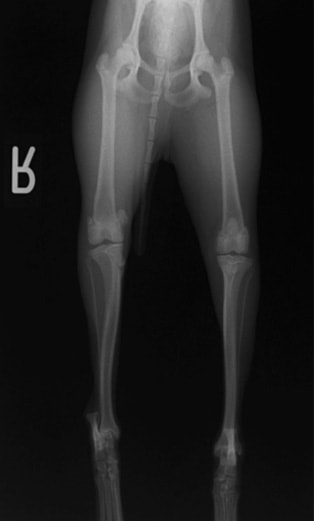

■ 症例24 キャバリア 7か月

左右膝蓋骨内方脱臼(左:グレードⅣ 右:グレードⅢ)

以前から左右後肢の跛行が認められ、整形外科学的検査・レントゲン検査により左右の膝蓋骨脱臼が認められた。症状が重度である左膝の膝蓋骨脱臼整復術を行った。外科手技は縫工筋及び内側広筋の解放、脛骨粗面の外側転位、滑車ブロック形造溝術、内外側関節方の縫縮を実施した。術後一か月時点で、左の膝蓋骨は安定しており経過は良好である。

本症例は成長期における重度の膝蓋骨脱臼であり、術後の再発の可能性もあるため、経過をしっかりと観察していく必要がある。また、今回手術を実施していない右膝に関しても経過を観察し、手術を検討していくこととする。